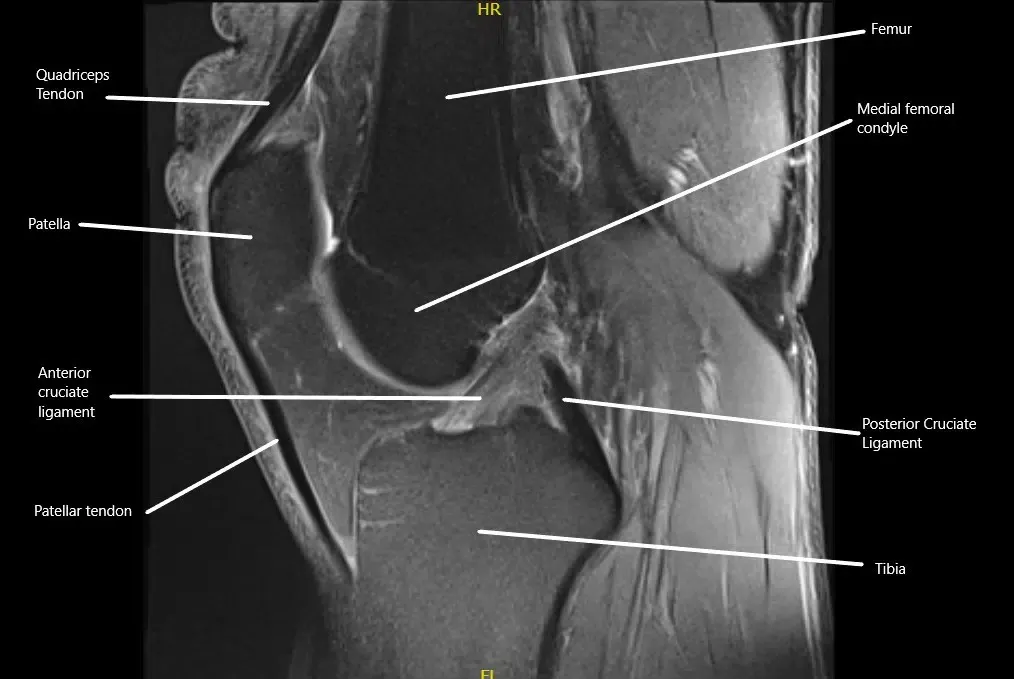

MRI showing the normal cruciate ligaments in the knee joint in the sagittal section.

The posterior cruciate ligament (PCL) is located inside the knee joint, connecting the back of the femur (thigh bone) to the front of the tibia (shinbone). It stabilizes the knee by preventing the tibia from moving too far backward relative to the femur. The PCL works with the anterior cruciate ligament (ACL) and other supporting structures to ensure the knee remains stable during movement, especially when bending or rotating.

Posterior cruciate ligament is located inside the knee and it attaches the lower end of femur to the upper end of tibia. It courses from the top and in the front to lower down on the back side of the upper end of tibia. It is present behind the anterior cruciate ligament.